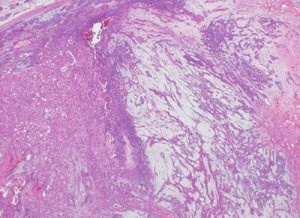

組織所見

耳下腺腫瘍の穿刺細胞診標本において癌細胞と多形腺腫由来の細胞を認めた。

唾液腺の悪性腫瘍は多形腺腫由来の可能性があることに留意して観察する必要がある。